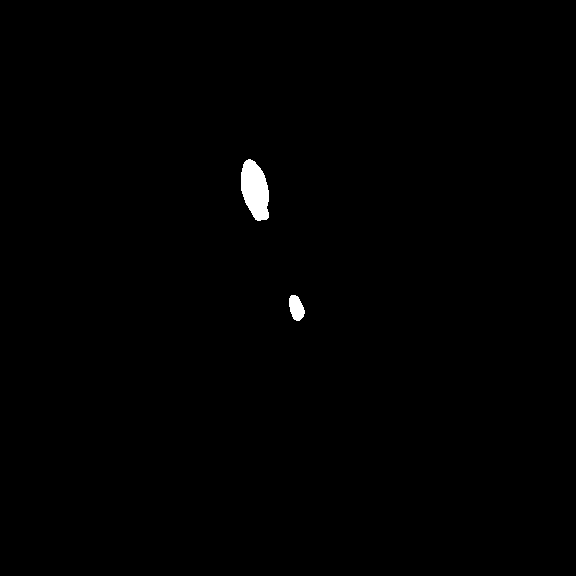

In terms of LA scar prediction, prior work predicts LA and LA scars separately without considering the relationship between them [16]. Meanwhile, the size of the scars is relatively insignificant, bringing difficulties in the prediction. Fortunately, LAs are much easier to be predicted, while LA scars are often detected near identified LA boundaries Fig. 2. Inspired by [29], we believe that combining the prediction of LAs and LA scars can be expected to improve scar segmentation performance.

We first trained the LA segmentation on task 2. The obtained model was loaded as the pre-training model for task 1. In detail, in the initial stage, the segmentation model was trained with all the LA labels available, obtaining the LA prediction model (LAPM). Then, we used the LAPM to roughly segment the targetted LA region, according to which images in the training set were cropped to train the scar prediction model (SPM). Specifically, the cropping region of interest (ROI) was implemented via , while , , , were boundary pixels of the predicted LA region, was an empirically-selected tolerance of LA prediction. Finally, the prediction map was restored to its original size using zero padding.

Figure 11 displays the prediction results with the two-stage prediction approaches and the normal ones. It can be clearly seen that the two stage method has successfully predicted most of the scars (see Fig. 11(c)), although some kind of false detection can still be observed. Nevertheless, with the common prediction method (see Fig. 11(f)), the scar is almost impossible to be predicted. We can hereby conclude that the two-stage prediction approach is essential in quantifying scars with irregular and tiny occupations on the picture.